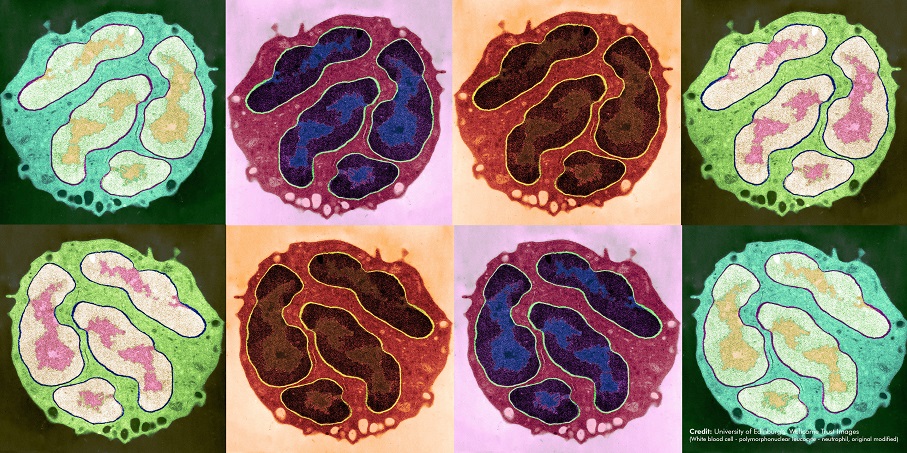

At the Wellcome Genome Campus we undertake both wet and dry lab science, basic research and the delivery of bioinformatics resources for the global scientific community.